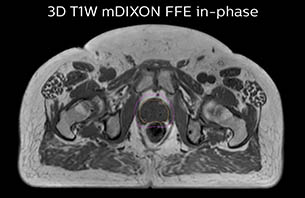

A 77-year-old male with prostate cancer cT3aN0M0, Gleason 8 and PSA 52 μg/L referred to androgen deprivation and radiation therapy with a prescribed dose of 50 Gy to the pelvic lymph node regions and 76 Gy to the prostate.

MR-only simulation workflow The 3D T1W FFE mDIXON sequence provides in-phase, water and fat images in one acquisition. Target and organs-at-risk are delineated on the 3D T2W TSE images. Prostate GTV is shown in orange, PTV in purple. The 3D bFFE sequence is used by the planner to mark the position of the fiducial markers (gold anchors) and contours are transferred to the digitally reconstructed radiographs (DRRs).

Based on the 3D T1W mDIXON images, MR-based density maps (MRCAT) are automatically generated. The VMAT (Volumetric Modulated Arc Therapy) plan is generated in TPS, based on MRCAT as primary image set. During the commissioning phase, dosimetric agreement between MRCAT-based and CT-based dose plans was studied and differences in the PTV dose were found to be minimal (<1% for most patients). Average difference in PTV mean values was 0.8% over the study group (n=62).